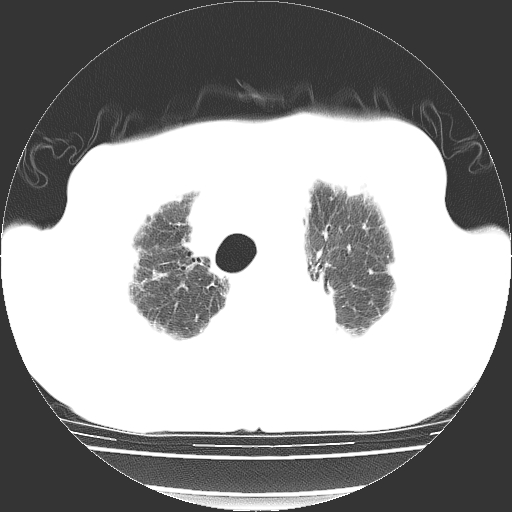

标题: CT25149:男,69岁,反复咳嗽、咳痰五年余,呼吸困难三天。 [打印本页]

男,69岁,反复咳嗽、咳痰五年余,呼吸困难三天。

慢支伴感染、肺气肿、肺心病

慢支伴感染、肺气肿、肺心病!支持!另:间质纤维化!

两肺间质性炎症并感染,左上叶肉芽肿

考虑慢性间质性肺炎并肺间质纤维化。

慢支伴感染、肺气肿、肺心病。双肺间质性改变(间质纤维化)。